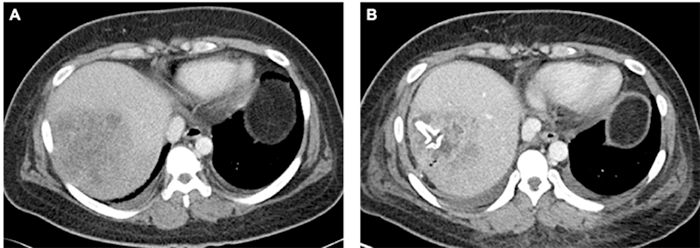

In the first case, a 25-year-old woman with insulin-dependent, type II diabetes mellitus who had immigrated to the United States from Southeast Asia 12 years previously presented with fever, vomiting, and right upper quadrant (RUQ) abdominal pain. She had a white blood cell count of 14,900 cells/mm3, random blood glucose of 293 mg/dL, hemoglobin A1c of 12.5 percent, total bilirubin of 0.7 mg/dL, alkaline phosphatase of 112 units/L, aspartate aminotransferase (AST) of 232 units/L, and alanine aminotransferase (ALT) of 267 units/L (Table 1). A RUQ ultrasonography revealed a hepatic mass, and a subsequent abdominal and chest computed tomography (CT) delineated a large, irregular, hypodense, heterogeneous lesion in the right lobe of the liver, consolidation of the right lower lobe (RLL) of the lung, and diffuse lung ground-glass opacities, consistent with a hepatic abscess and an RLL pneumonia. Ultrasonographically-guided percutaneous drainage with a 5 French Yueh catheter was attempted; however, only 1 mL of viscous fluid could be aspirated. Due to initial concern for malignancy, a core needle biopsy was performed, which performed. These findings revealed no evidence of malignancy and instead were consistent with a hepatic abscess. Two days after admission, the patient began to clinically decompensate with increasing oxygen requirements, tachycardia up to 109 beats per minute, and blood pressure of 80/50 mmHg; blood cultures were drawn and demonstrated gram-negative bacteremia. The patient was then transferred to our intensive care unit (ICU) to manage septic shock, diabetic ketoacidosis, and acute hypoxic respiratory failure due to sepsis and RLL pneumonia. A hypermucoviscous strain of Klebsiella pneumoniae was isolated from the sputum. The patient failed to improve despite treatment with IV vancomycin and piperacillin/tazobactam. Repeat CT seven days later demonstrated enlargement of the hepatic abscess to 8.9 cm from 7.3 cm in the largest diameter (Figure 2A). After discussions among members of the infectious disease division, surgery, and interventional radiology, operative drainage was considered the optimal approach for this patient. The patient underwent laparoscopic-assisted, percutaneous, transperitoneal drainage of the abscess using a 26 French Malecot catheter placement into the abscess cavity, which drained approximately 40 mL of thick purulent material. A tongue of omentum was mobilized to wrap around the Malecot catheter to minimize leakage of purulent fluid into the abdominal cavity and avoid displacement of the catheter. Klebsiella pneumoniae was isolated from cultures obtained from the hepatic abscess and was found to have a positive string test (Figure 1). The patient clinically improved rapidly with gradual resolution of fever and leukocytosis. CT on postoperative day 7 demonstrated a 3 cm decrease in the size of the abscess (Figure 2B). The patient completed a six-week course of outpatient IV ceftriaxone. The Malecot catheter was removed seven weeks after placement.

Figure 2. Radiographic Images From Case 1. Published with Permission

A) Transverse section of CT chest/abdomen/pelvis from Case 1 obtained 9 days after admission and 2 days before surgery demonstrating 8.9 cm × 8.0 cm × 7.8 cm heterogenous, complex collection in right hepatic lobe; B) transverse section of CT chest/abdomen/pelvis from Case 1 obtained 7 days after surgery with contrast demonstrating slight decrease in size of right hepatic abscess, measuring 8.0 cm × 5.0 cm × 7.0 cm. Drainage catheter with intrahepatic tip is visualized